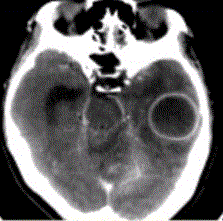

问题 患者女,26岁,头痛、低热10d余,既往有左侧慢性中耳炎病史。CT表现如下图。 脑脓肿的MRS表现,正确的是

选项 A.Cho明显升高 B.NAA未见异常 C.Lac升高 D.乙酸峰、乳酸峰、丁二酸峰升高 E.Lip峰升高

答案 D